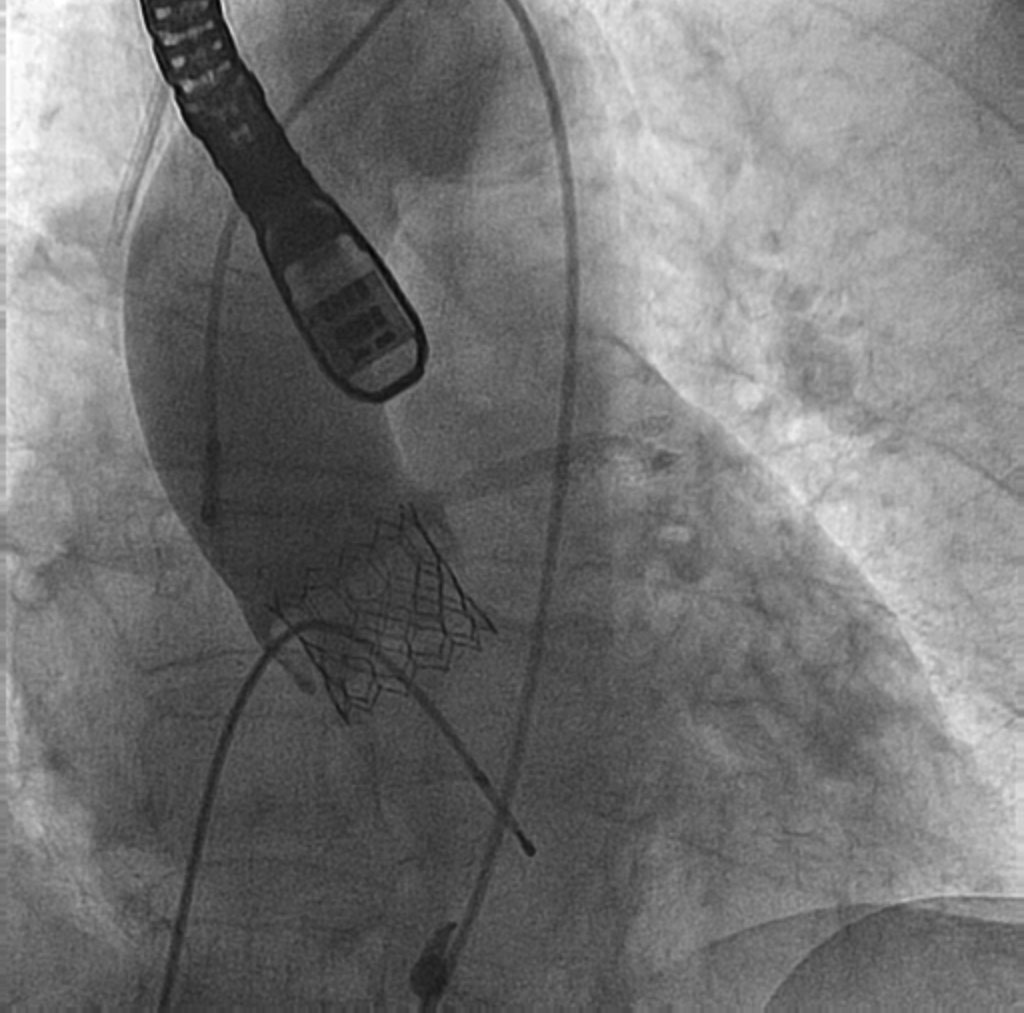

El procedimiento se efectuó bajo anestesia general, mediante abordaje femoral bilateral. Se colocaron 2 catéteres guía Extra Back Up (EBU) de 3,5 mm, de 6 y 7 Fr, en el tronco común izquierdo (técnica ping-pong). Se realizó predilatación secuencial de los ostia coronarios de la descendente anterior y las ramas intermedias mediante un balón de corte de 2,0 mm (vídeo 1 del material adicional) y se implantaron simultáneamente 3 stents farmacoactivos en la descendente anterior (stent liberador de sirolimus, de 2,25 × 15 mm), la primera rama intermedia (stent liberador de zotarolimus, de 2,25 × 18 mm) y la segunda rama intermedia (stent liberador de sirolimus, de 2,25 × 18 mm), por este orden; posteriormente se realizó un inflado simultáneo (figura 2). Por disección retrógrada se implantó un cuarto stent farmacoactivo (stent liberador de zotarolimus, de 4 × 8 mm) en el tronco común izquierdo (figura 3 y vídeo 2 del material adicional), con buen resultado por tomografía de coherencia óptica (figura 4A, B). Inmediatamente después de la intervención coronaria percutánea (ICP) se implantó una válvula aórtica expandible con balón de 23 mm (figura 5 y vídeo 3 del material adicional), también con buen resultado (figura 6 y vídeo 4 del material adicional).

Figura 3. Implante de un stent farmacoactivo en el tronco común izquierdo.